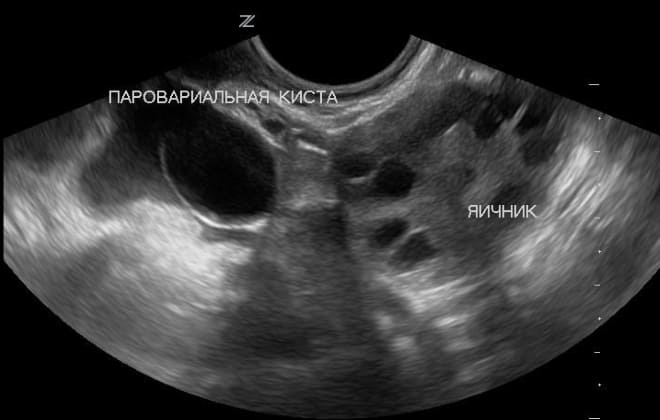

Киста может быть выявлена только в том случае, если её размер превышает 2 см. Сначала врач проводит пальпацию брюшной полости пациентки, после чего она направляется на ультразвуковое обследование.

Ультразвуковая диагностика является ключевым методом для выявления данного заболевания. Если образование достигает 3 см и больше, то определить его местоположение и характеристики становится достаточно просто.

Как диагностируется параовариальная киста у беременных женщин?

Диагностика параовариальной кисты у беременных женщин обычно проводится с помощью ультразвукового исследования (УЗИ). Этот метод безопасен для матери и плода и позволяет точно определить наличие кисты, ее размер и расположение, а также оценить возможные риски.